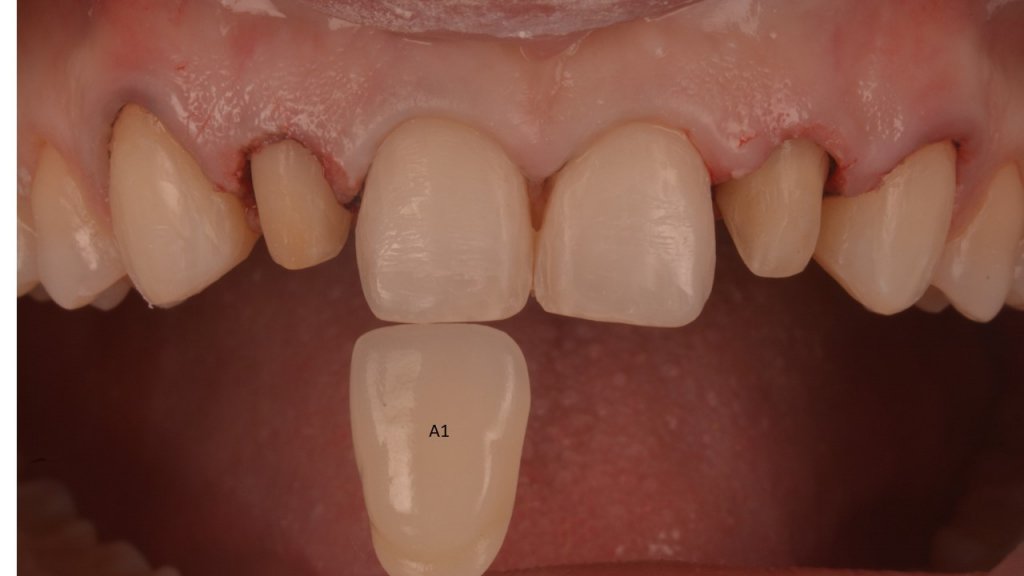

El momento más «bonito» para ti, para la paciente, para la auxiliar (Karla), y para Nacho…a ver si no rompemos sus MARAVILLAS (pero la culpa es siempre mía, que tallo cada vez menos)

Y vamos de Azul (NIC TONE) sin linea de terminación, sufrimos el doble..no tenemos donde agarrar el Clamp y sobre todo donde realmente termina la carilla…

Voy siempre de 2 en 2, claramente cemento antes las Coronas, que me ayudaran a «clampar» y luego las carillas. Pero normalmente empiezo con los laterales que están en el medio y suelen robar el espacio a los otros